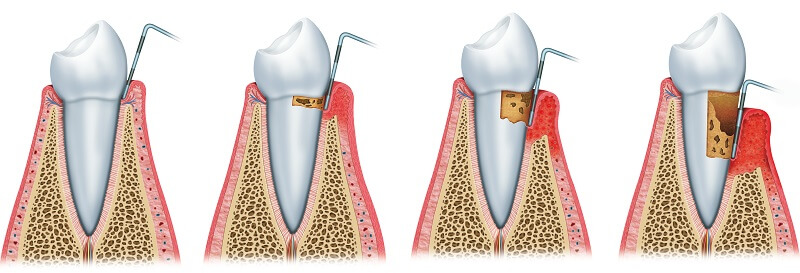

Що таке пародонтоз?

Пародонтоз - це ураження кісткової тканини навколо зуба, яке супроводжується її зменшенням, за відсутності ознак запалення. Дехто помилково вважає, що пародонтоз - це ускладнення пародонтиту. Але це не так, спільним для цих захворювань є лише локалізація, а саме пародонт, комплекс тканин, що оточує та утримує зуб.

При пародонтозі відсутні ознаки запалення: ясна зберігають нормальний вигляд та не кровоточать. Найпоширенішим симптомом, що може свідчити про захворювання є оголення коренів зубів, що супроводжується ниттям.

- Виникає пародонтальна кишеня, куди потрапляють залишки їжі;